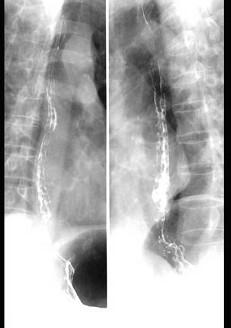

问题 下列各图最佳的诊断是 ( )

选项 A、食管静脉曲张 B、以上都不是 C、食管憩室 D、贲门失弛症 E、食管癌

答案 A